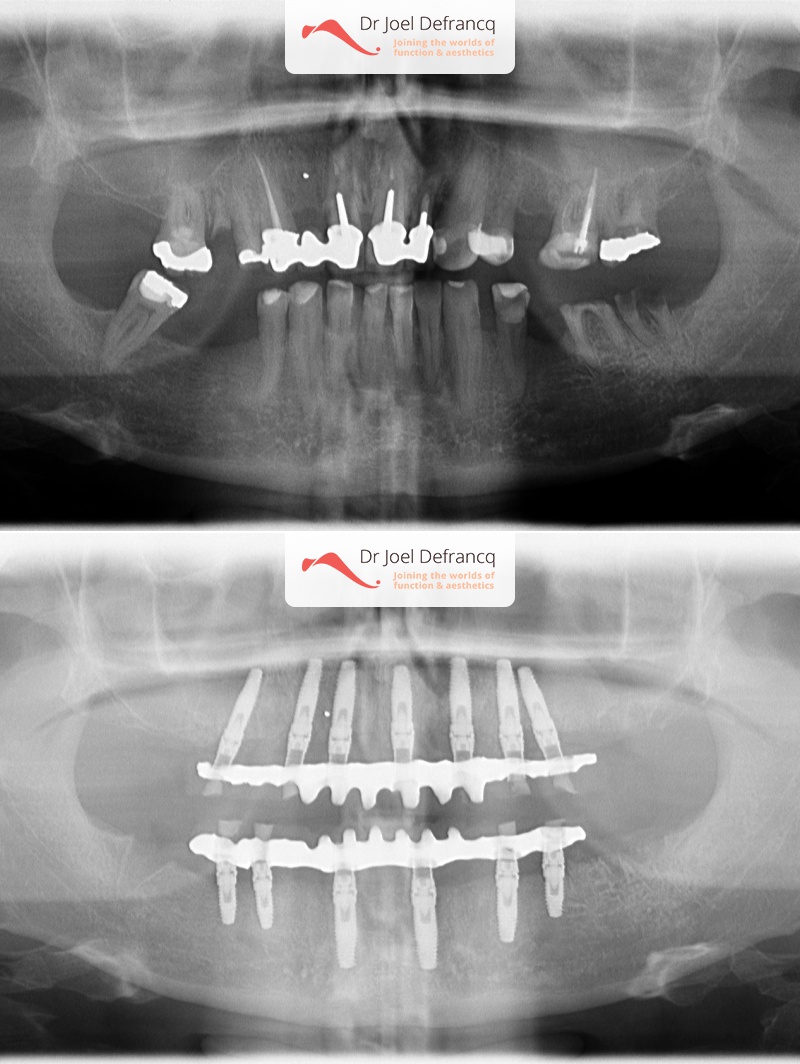

Veli: new teeth in a week - implants.

Dentale diagnose

- Klasse I

Behandeling tandheelkundige implantaten

- Vaste tanden op implantaten (bovenkaak)

- Vaste tanden op implantaten (onderkaak)